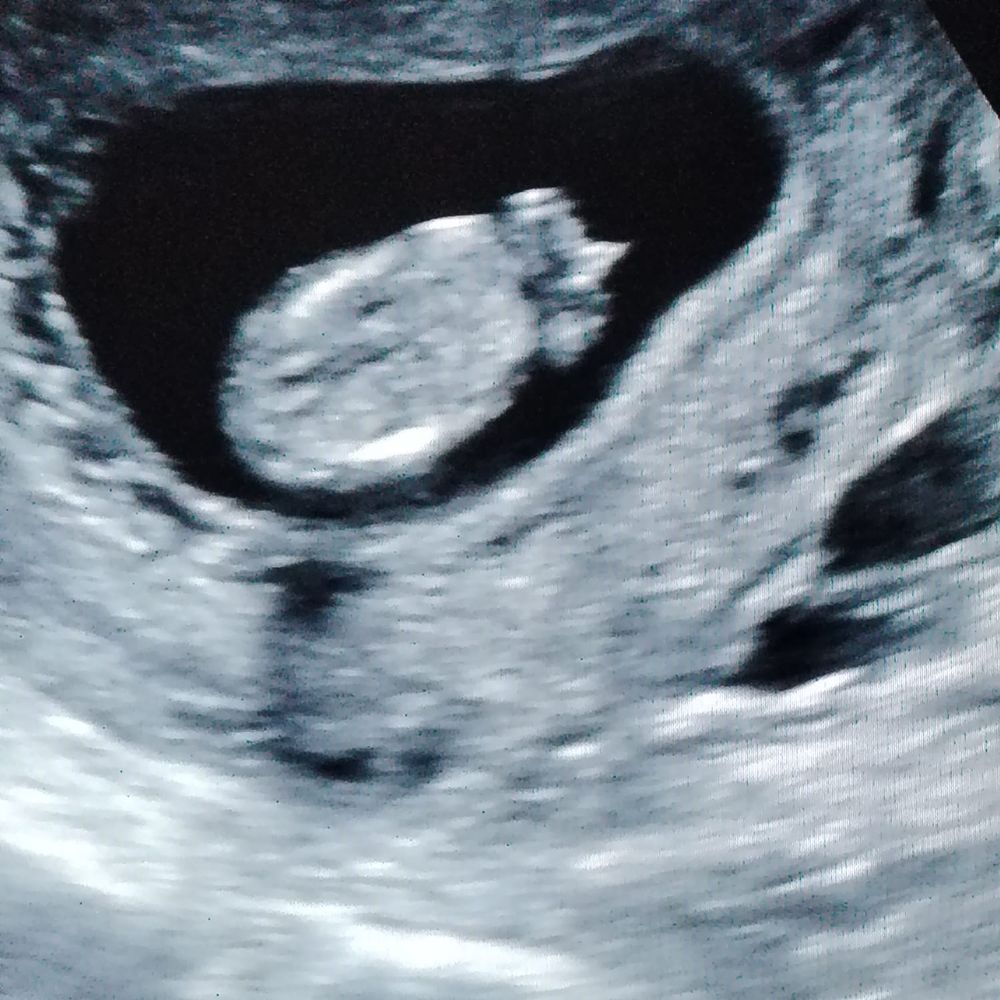

Евгения , Изображение Изображение

16.12.2024

Евгения , вот такие только) вот обвели и говорят мальчик)

Ирина Качанова, неудачные фото узи. Жаль что нет других

Ирина Качанова, если бы сбоку фото было еще можно было бы предположить( тут будто сверху лялю сфоткали